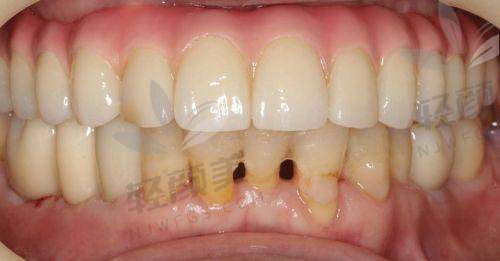

有人说,种植牙这项目,是牙科界的“豪车”——价格高、操作精、材料贵。但在贝壳口腔,种牙也能走“性价比路线”。以下是根据法定数据和实地探访,整理出的2026价目明细:

种植牙价目表(单颗)

▪ 韩国登腾:3988元起

▪ 韩国奥齿泰:4680元起

▪ 美国皓圣:5280元起

▪ 瑞士ITI:6980元起

▪ 德国费亚丹:8680元起

▪ 瑞典诺贝尔:9500元起

划重点:以上价格包括牙冠+种植体+基台,有些医院会偷偷只标“种植体价格”,结果“牙冠另收3800,基台另算1500”,到账单才发现多花了5000块。还没唤醒医疗保险,钱包已经睡着……贝壳口腔各分院在面诊当天会打印详细账单列表,让费用变得“看得见,摸得着”!